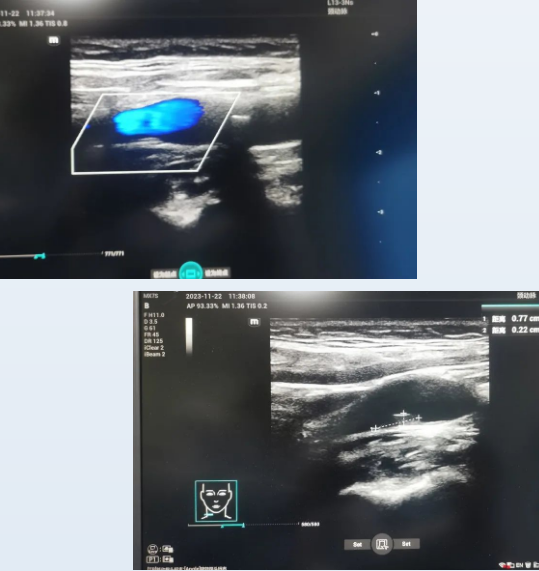

医学影像学利用各种影像技术手段,通过检查来延伸医生的"视力"获得患者体内结构影像信息,帮助医生对病灶的定位定性,为临床及时采取治疗措施指明方向,其中,B超就是一项非常重要的影像检查方法。B超检查的优势主要包括无创、安全、准确率高、实时动态观察以及可以反复进行。

为了满足周边居民的就医需要,星城三里社区卫生服务站于今年11月中旬引进了新型的B超机,并聘请了三级医院B超室的大夫为大家服务,检查项目较为全面,包括各种脏器、动静脉血管、腺体、及体表肿物等方面,检查时间为每周三及周五上午8点~12点,方便大家在家门口就能得到高质量、高水平的诊疗服务。